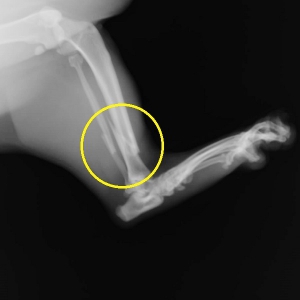

早速ですが、下写真が当院で撮影をやり直した骨折のレントゲン写真です。右写真が「スネの骨」側面から、左が正面像です。「くるぶし」のちょっと上に斜めに大きくずれた骨折が見られます。(黄色丸の中)

骨折は脛骨(スネの骨)の骨折とそのお隣の細い骨、腓骨の(骨が外に出ていない)単純骨折です。通常、腓骨は脛骨とともに折れますから、以下、まとめて脛骨骨折とします。

骨折の分類としては骨に対して斜めに骨折線が走る、斜骨折と言います。また、骨折部位が骨の端にあるため、部位的には「遠位端骨折」といいます。遠位端の斜骨折は整復の難しい骨折のひとつです。